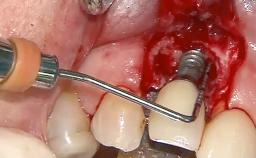

A 79-year-old female patient was referred to the Department of Periodontology of the University of Bern, Switzerland by her private dentist in May 2019. She had been rehabilitated in May 2005 with two tissue-level implants (Institut Straumann AG, Basel Switzerland) at sites 13 and 15, supporting a three-unit cemented fixed dental prosthesis (FDP). The metal-ceramic FDP had been cemented permanently with a glass-ionomer cement (Ketac Cem; 3M ESPE, Seefeld, Germany). Implant 13 had been diagnosed with peri-implant mucositis by the referring dentist in the course of regular supportive therapy. The patient was in good general health, did not smoke, and exhibited good self-performed plaque control.